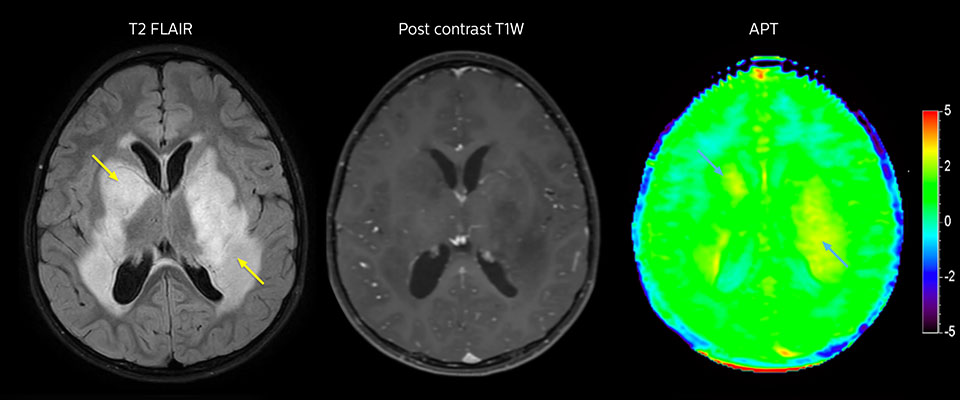

Niedrig differenziertes Gliom bei einem 5-jährigen Patienten mit Neurofibromatose 1. Diese niedrig differenzierte Läsion zeigt auf kontrastverstärkten Bildern keine Anreicherung, aber ein mittelgradiges APT-Signal. Die Stabilität der Läsion über die Zeit bestätigt, dass es sich um eine pathologische Veränderung niedriger Differenzierung handelt.